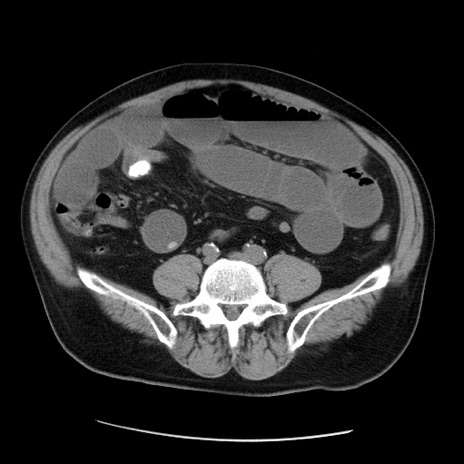

症例20(横断像)

【症例】 60歳代男性

【主訴】 腹部膨満、嘔吐

【現病歴】5日前頃より倦怠感を認め食事量減少し4日前の朝嘔吐、食事摂取困難となった。 3日前近医受診し点滴施行され整腸剤などを処方された。 当日他院を受診し、腹部膨満著明、炎症反応の上昇(CRP10.8、WBC11200)あり、紹介受診となる。

【身体所見】 意識JCS1 受け答えがはっきりしないBP 111/57mHg、 P 67bpm、、BT35.2°C、SpO2 97%(RA)、 腹部:膨隆、打診で鼓音あり、全体的に圧痛有り、腸蠕動音(-)、反跳痛ははっきりせず。

【データ】WBC 11400、CRP 14.20